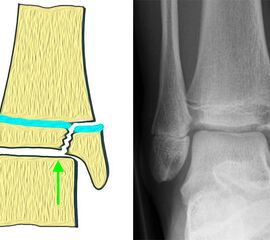

Allerdings bietet der zelluläre Anteil der Epiphysenfuge einen geringeren Widerstand gegenüber Scher-und Biegungskräften. Der wachstumsaktive, epiphysäre Teil der Fuge wird bei der Fugenschaftfraktur allenfalls geringfügig geschädigt, da der Frakturverlauf die wachstumsaktive Zellschicht nicht tangiert (Aitken I, Fugenschaftfraktur).

Bei relevanten Axialtraumata kreuzt der Frakturspalt den epiphysären Anteil der Wachstumsfuge (Fugengelenkfraktur, Aitken II und III), mit entsprechenden Risiko das Wachstum zu beeinflussen. Die verschiedenen Klassifikationssysteme der Frakturen im Wachstumsalter sind in Abbildung 2 45 dargestellt.

Mediale Malleolarfrakturen

Bei den medialen Malleolarfrakturen handelt es sich um Fugengelenkfrakturen bzw. Aitken II und III Verletzungen. Kennzeichnend ist, dass der Frakturverlauf die wachstumsaktive Zone zur Epiphyse hin durchkreuzt. Die Verletzung der wachstumsaktiven Zone macht diese Verletzungen besonders problematisch.

Fugengelenkfrakturen treten typischerweise vor dem 10. Lebensjahr auf, in einer Phase, in welcher die Wachstumsfugen noch weit offen sind. Dieser Frakturtyp betrifft fast ausschließlich den medialen Malleolus. Laterale Frakturen sind extrem selten, teilweise kommt es zu lateralen Bandverletzungen oder Fugenschaftfrakturen der distalen Fibula. Die Frakturlinie verläuft in einer Verlängerungslinie von der medialen Taluskante nach proximal. Häufig stellen sich Verletzungen des Innenknöchels im Röntgenbild schlechter dar, insbesondere wenn die Aufnahmen verdreht sind oder die Ebene der Fraktur bei geringer Dislokation verkippt zur Röntgenebene liegt. Besteht klinisch der geringste Hinweis auf eine Verletzung des Innenknöchels, muss aufgrund der Tragweite der Verletzung durch entsprechende Aufnahmen gegebenenfalls auch Schnittbildverfahren die Verletzung sicher diagnostiziert oder ausgeschlossen werden (Abb. 15).

Fugengelenkfrakturen können die Wachstumsfuge durchkreuzen (Abbildung 16a), ohne oder nur mit minimaler Beteiligung der Fuge sehr weit medial liegen (Abbildung 16b) oder durch die Fuge auslaufen (Abbildung 16c). Relevant für die Wachstumsprognose ist weniger die Form der Fraktur, sondern das Alter des Patienten zum Zeitpunkt des Traumas sowie das Ausmaß der Schädigung der Wachstumsfuge, wobei eine Korrelation mit dem Ausmaß der Dislokation besteht.